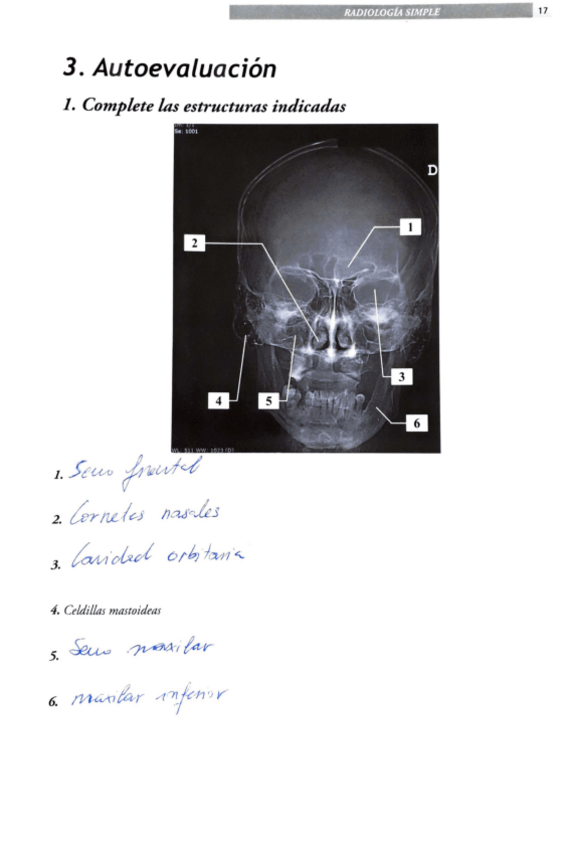

Ejercicios - Libro-Radiologia-Anatomia-corregido.pdf

17